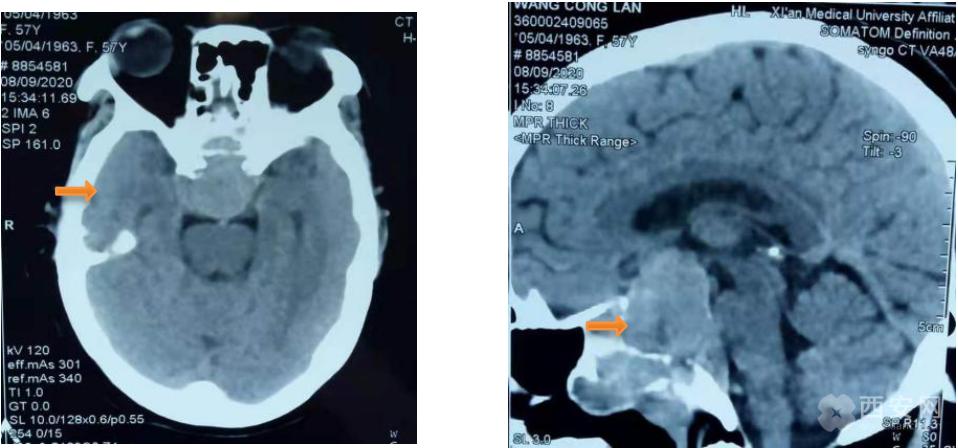

(头颅CT可见鞍区巨大占位性病变 颅底骨质结构破坏)

检查结果显示为巨大侵性垂体腺瘤,肿瘤生长向上突入鞍上池,向下突破鞍底蝶窦进入鼻腔破坏颅底斜坡骨质,大小约31×38×32mm,属于罕见的巨大型侵袭性垂体腺瘤。